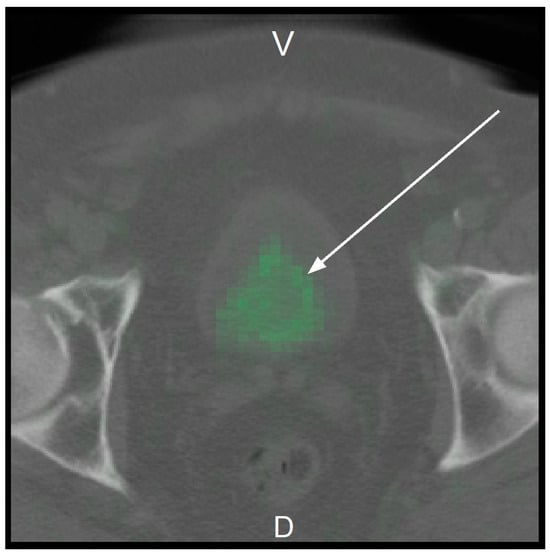

The previously cropped NIfTIs were then used in the training of Model 2. The cropped image area can be seen as a CT image with PET image overlay in the following Figure A1.

Figure A1. Cropped NIfTI of pseudo ID 00045.

Cancers 17 01575 g0a1

Cropped NIfTI of pseudo ID 00045 with one channel as CT (greyscale) and one channel as PET (green). The ventral side of the patient (V) is on the top, while the dorsal side of the patient (D) is at the bottom of the Figure. The right hip bone is on the left side of the image, while the left hip bone is on the right side of the image. The Figure is in perspective, as if one were looking towards the head of the patient. The arrow points to the prostate (area).

As in Model 1, after sorting out the incorrect NIfTIs and the cases in which the label is 3, the data set had a size of 1138. Similarly, the size of the training set was 957 and the size of the validation set was 181. The training transforms and the validation transforms were identical to those in Model 1, with one difference: in function Resized(), instead of a spatial_size of (150, 150, 150), a spatial_size of (70, 70, 70) was used to enable the batch size to be increased from 8 to 16.